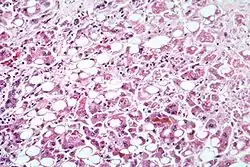

Alcoholic hepatitis as seen with a microscope, showing fatty changes (white circles), remnants of dead liver cells, and Mallory bodies (twisted-rope shaped inclusions within some liver cells). (H&E stain)

Steatohepatitis is seen in both alcoholic and non-alcoholic liver disease and is the culmination of a cascade of events that began with injury. In the case of non-alcoholic steatohepatitis, this cascade is initiated by changes in metabolism associated with obesity, insulin resistance, and lipid dysregulation.[66][67] In alcoholic hepatitis, chronic excess alcohol use is the culprit.[68] Though the inciting event may differ, the progression of events is similar and begins with accumulation of free fatty acids (FFA) and their breakdown products in the liver cells in a process called steatosis.[66][67][68] This initially reversible process overwhelms the hepatocyte's ability to maintain lipid homeostasis leading to a toxic effect as fat molecules accumulate and are broken down in the setting of an oxidative stress response.[66][67][68] Over time, this abnormal lipid deposition triggers the immune system via toll-like receptor 4 (TLR4) resulting in the production of inflammatory cytokines such as TNF that cause liver cell injury and death.[66][67][68] These events mark the transition to steatohepatitis and in the setting of chronic injury, fibrosis eventually develops setting up events that lead to cirrhosis and hepatocellular carcinoma.[66] Microscopically, changes that can be seen include steatosis with large and swollen hepatocytes (ballooning), evidence of cellular injury and cell death (apoptosis, necrosis), evidence of inflammation in particular in zone 3 of the liver, variable degrees of fibrosis and Mallory bodies.[66][69][70]